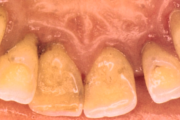

Krooniline parodontiit

Krooniline parodontiit on mikroobide poolt põhjustatud hammaste tugikudede põletik, mille tulemusena tekib progresseeruv alveolaarluu (nähtav röntgenograamil) ja periodontaalligamendi destruktsioon, igemetaskute moodustumine, igeme retsessioon või mõlemad kahjustused kombineeritult. Loe edasi »

- igemed veritsevad (19)

- igemed punetavad (21)

- ige on paistes (mädapunn)

- igemed on tursunud/vohavad (17)

- igemepiir on taandunud (3)

- luu destruktsioon (5)

- vahed hammaste vahel (5)

- hammaste tundlikkus (9)